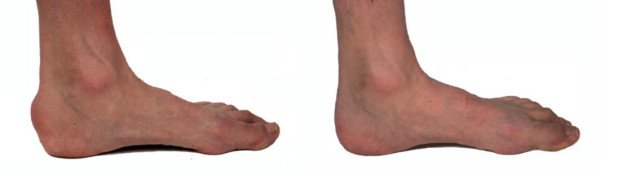

Die Haglund-Ferse, im Volksmund auch «Überbein» genannt, wird durch eine Deformation des Fersenbeins verursacht, das auf seiner Rückseite herausstehend ausgebildet ist und so zu chronischem Druck im Schuh führen kann. Die chronische Schleimbeutelentzündung, die sich dadurch entwickelt, kann ein groteskes Ausmass annehmen und das Tragen von geschlossenen Schuhen zur Qual werden lassen.

Nach zwei bis drei Tagen kann der Patient das Spital verlassen und ist an Stöcken mobil. Es folgt eine etwa sechswöchige Phase der Teilbelastung, anschliessend ein rascher Belastungsaufbau. Wir konnten beobachten, wie sich sogar schwer veränderte und chronisch entzündete Sehnen erholten, nachdem sie sozusagen «befreit» worden sind.